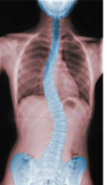

Spinal column develops an ___-shape as infant grows

s

Primary curvatures

thoracic and sacral curves present during fetal period

Secondary curvatures

Cervical curvature - allows us to hold our heads up

Lumbar curvature - shifts weight of body onto sacrum

Scoliosis

lateral curvatures in vertebral column

exaggerated cervical and lumbar curvatures

Lordosis (swayback)

Kyphosis (hunchback)

exaggeration of thoracic curvature

Lordosis

Kyphosis